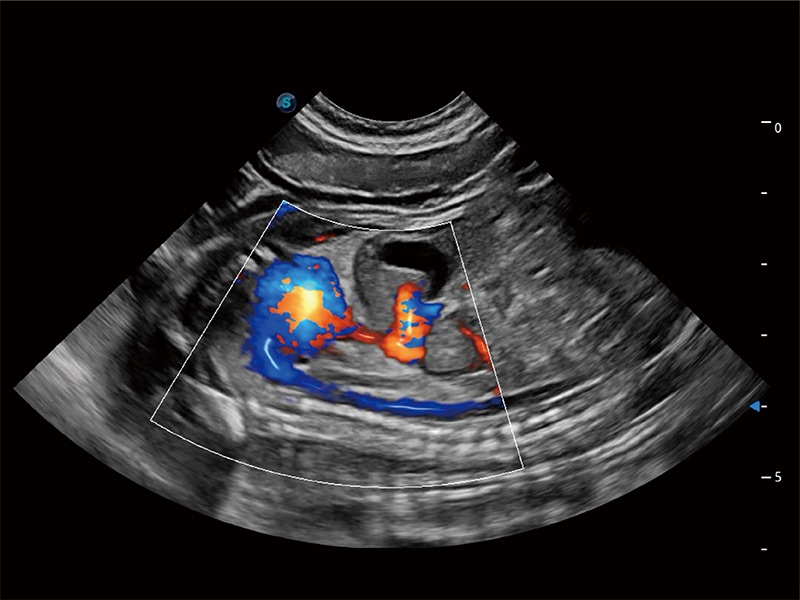

(犬)胎儿四腔心